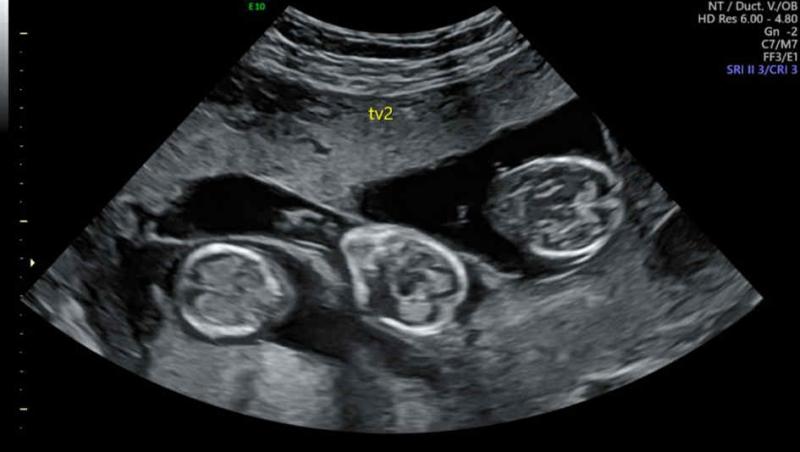

Chiar dacă medicii i-au dat șanse puține, Marie a reușit să rămână însărcinată cu tripleți. | Profimedia

Chiar dacă medicii i-au sfătuit să nu facă embriotransfer cu trei embrioni din cauza riscurilor asociate, Marie și soțul ei și-au asumat acest risc. Astfel, ei au devenit de curând părinții unor tripleți.

„În timpul celorlalte sarcini ale mele nu am avut deloc probleme și am rămas însărcinată destul de rapid, dar acum, având în vedere vârsta mea, nu am crezut că va fi așa rapid. De aceea am decis să transferăm trei embrioni pentru a ne crește șansele. Medicii au spus că există o șansă de 5% ca să rămân însărcinată, dar până la urmă toți cei trei embrioni s-au implantat. Am fost atât de șocată și fericită. A fost un dar extraordinar”, a mai spus Marie.

Tripleții s-au născut prin cezariană, iar Charlie a cântărit 1,5 kg, Lorinne a avut la naștere 1,3 kg, iar Lara doar 1 kg.